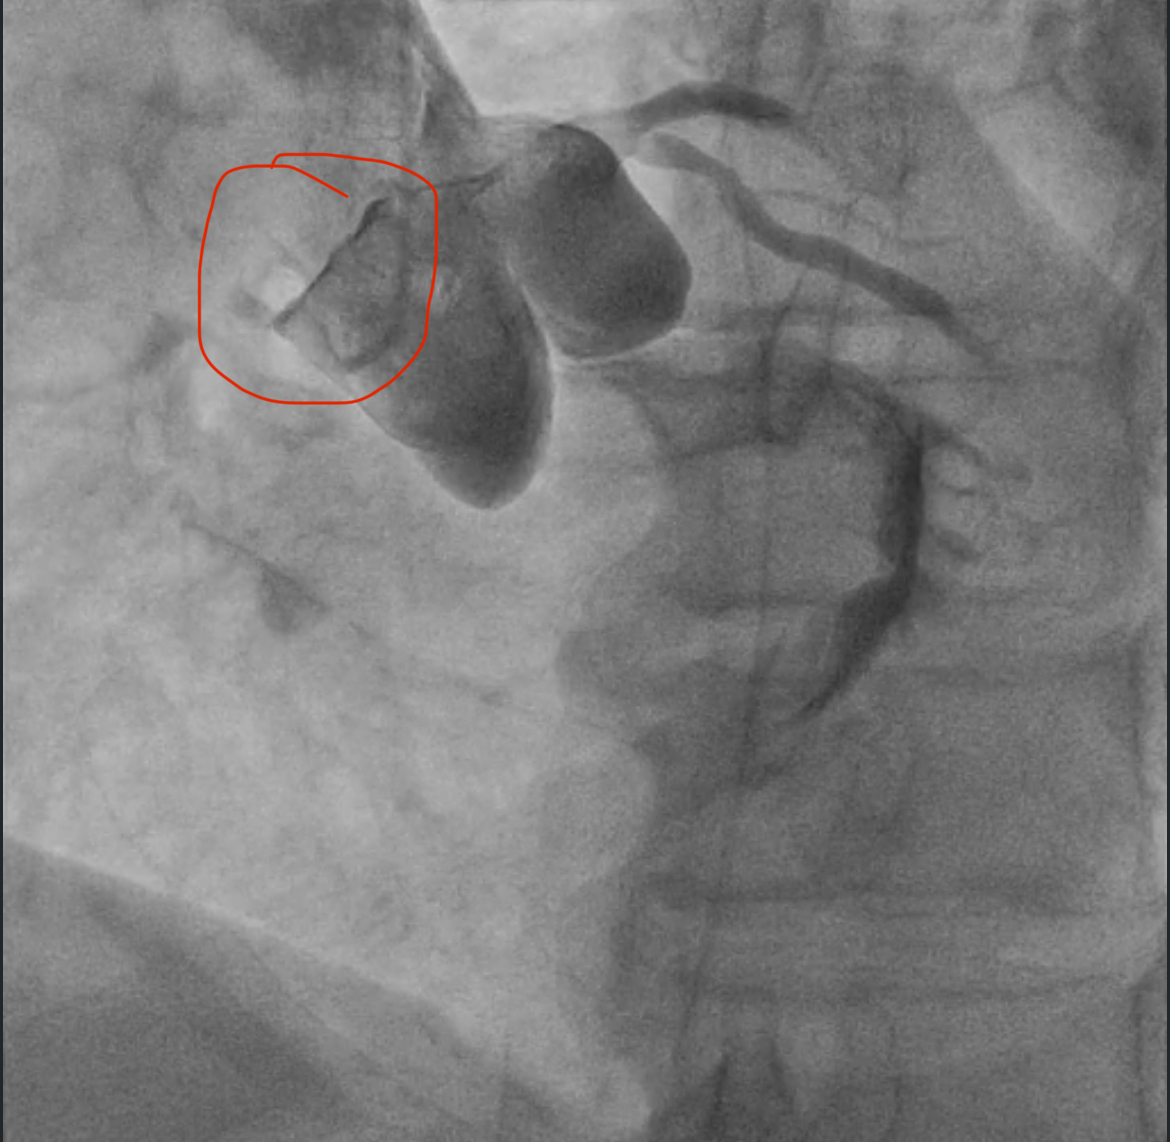

8 утра, мужчина 66 лет, боли в груди с 3 ночи, скорая, в машине 7 раз фибрилляция желудочков, ЭДС, перевод на ИВЛ, с приемника на стол на коронарографию, при перекладывании опять остановка, наружный массаж, адреналин, ЭДС, пункция по ориентирам, введен катетер и такая картина - закрыты все три артерии, сердце стоит, на ЭКГ электрическая активность сохранялась еще минут 15 (электромеханическая диссоциация). На вскрытии циркулярный инфаркт, шоковые органы.